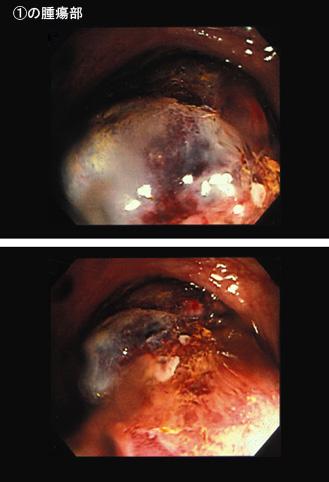

Tejido grasoso del Colon, que acompaña úlceras en la intusucepción y sus alrededores

Tumor no Epitelial Benigno/Lipoma

colon/descendente

Endoscopia

35 - 40